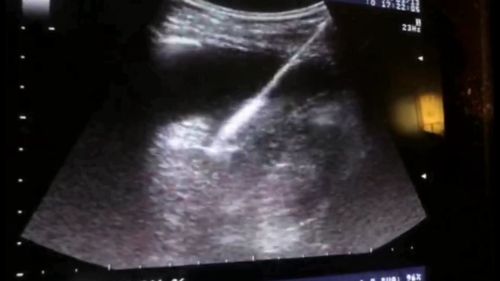

在B超引导下,微波针经皮-胸腔-肝直捣肿瘤。

胆道外二科主任汪新天教授、陈晨副主任医师、超声科赵康副主任医师、王永主治医师等组成的医疗团队反复讨论,制定了周密的手术方案。在汪新天教授指导下,陈晨医疗团队为刘先生实施B超引导下经皮肝穿刺肝肿块微波消融术。

术中发现,患者肿瘤穿刺的位置比较刁钻,手术难度比术前预计的要大很多。医疗团队反复商讨后,决定施行经皮-胸腔-肝穿刺肝肿块微波消融术。在彩超引导下,往右侧胸腔注射生理盐水1400ml,让肺尖给消融针让位;再次B超定位,经胸腔穿刺进针至肿瘤部位。终于成功将肿瘤消融干净,术中出血仅2ml。术后当天,患者就能下床活动,并很快恢复正常,没有并发症,术后第二天出院。